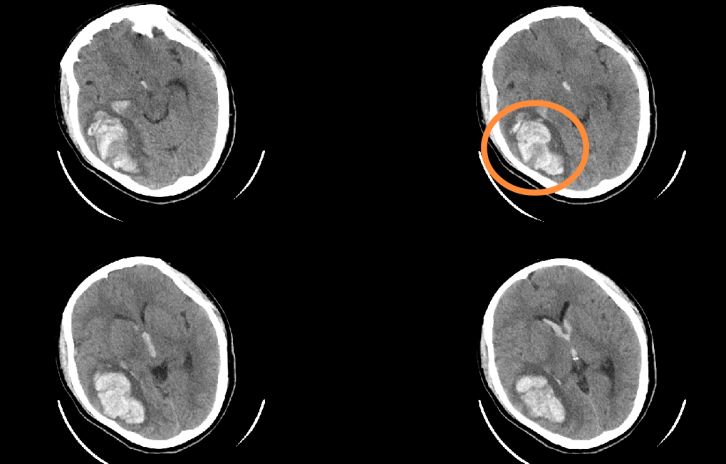

術(shù)前CT影像(白色為血腫)